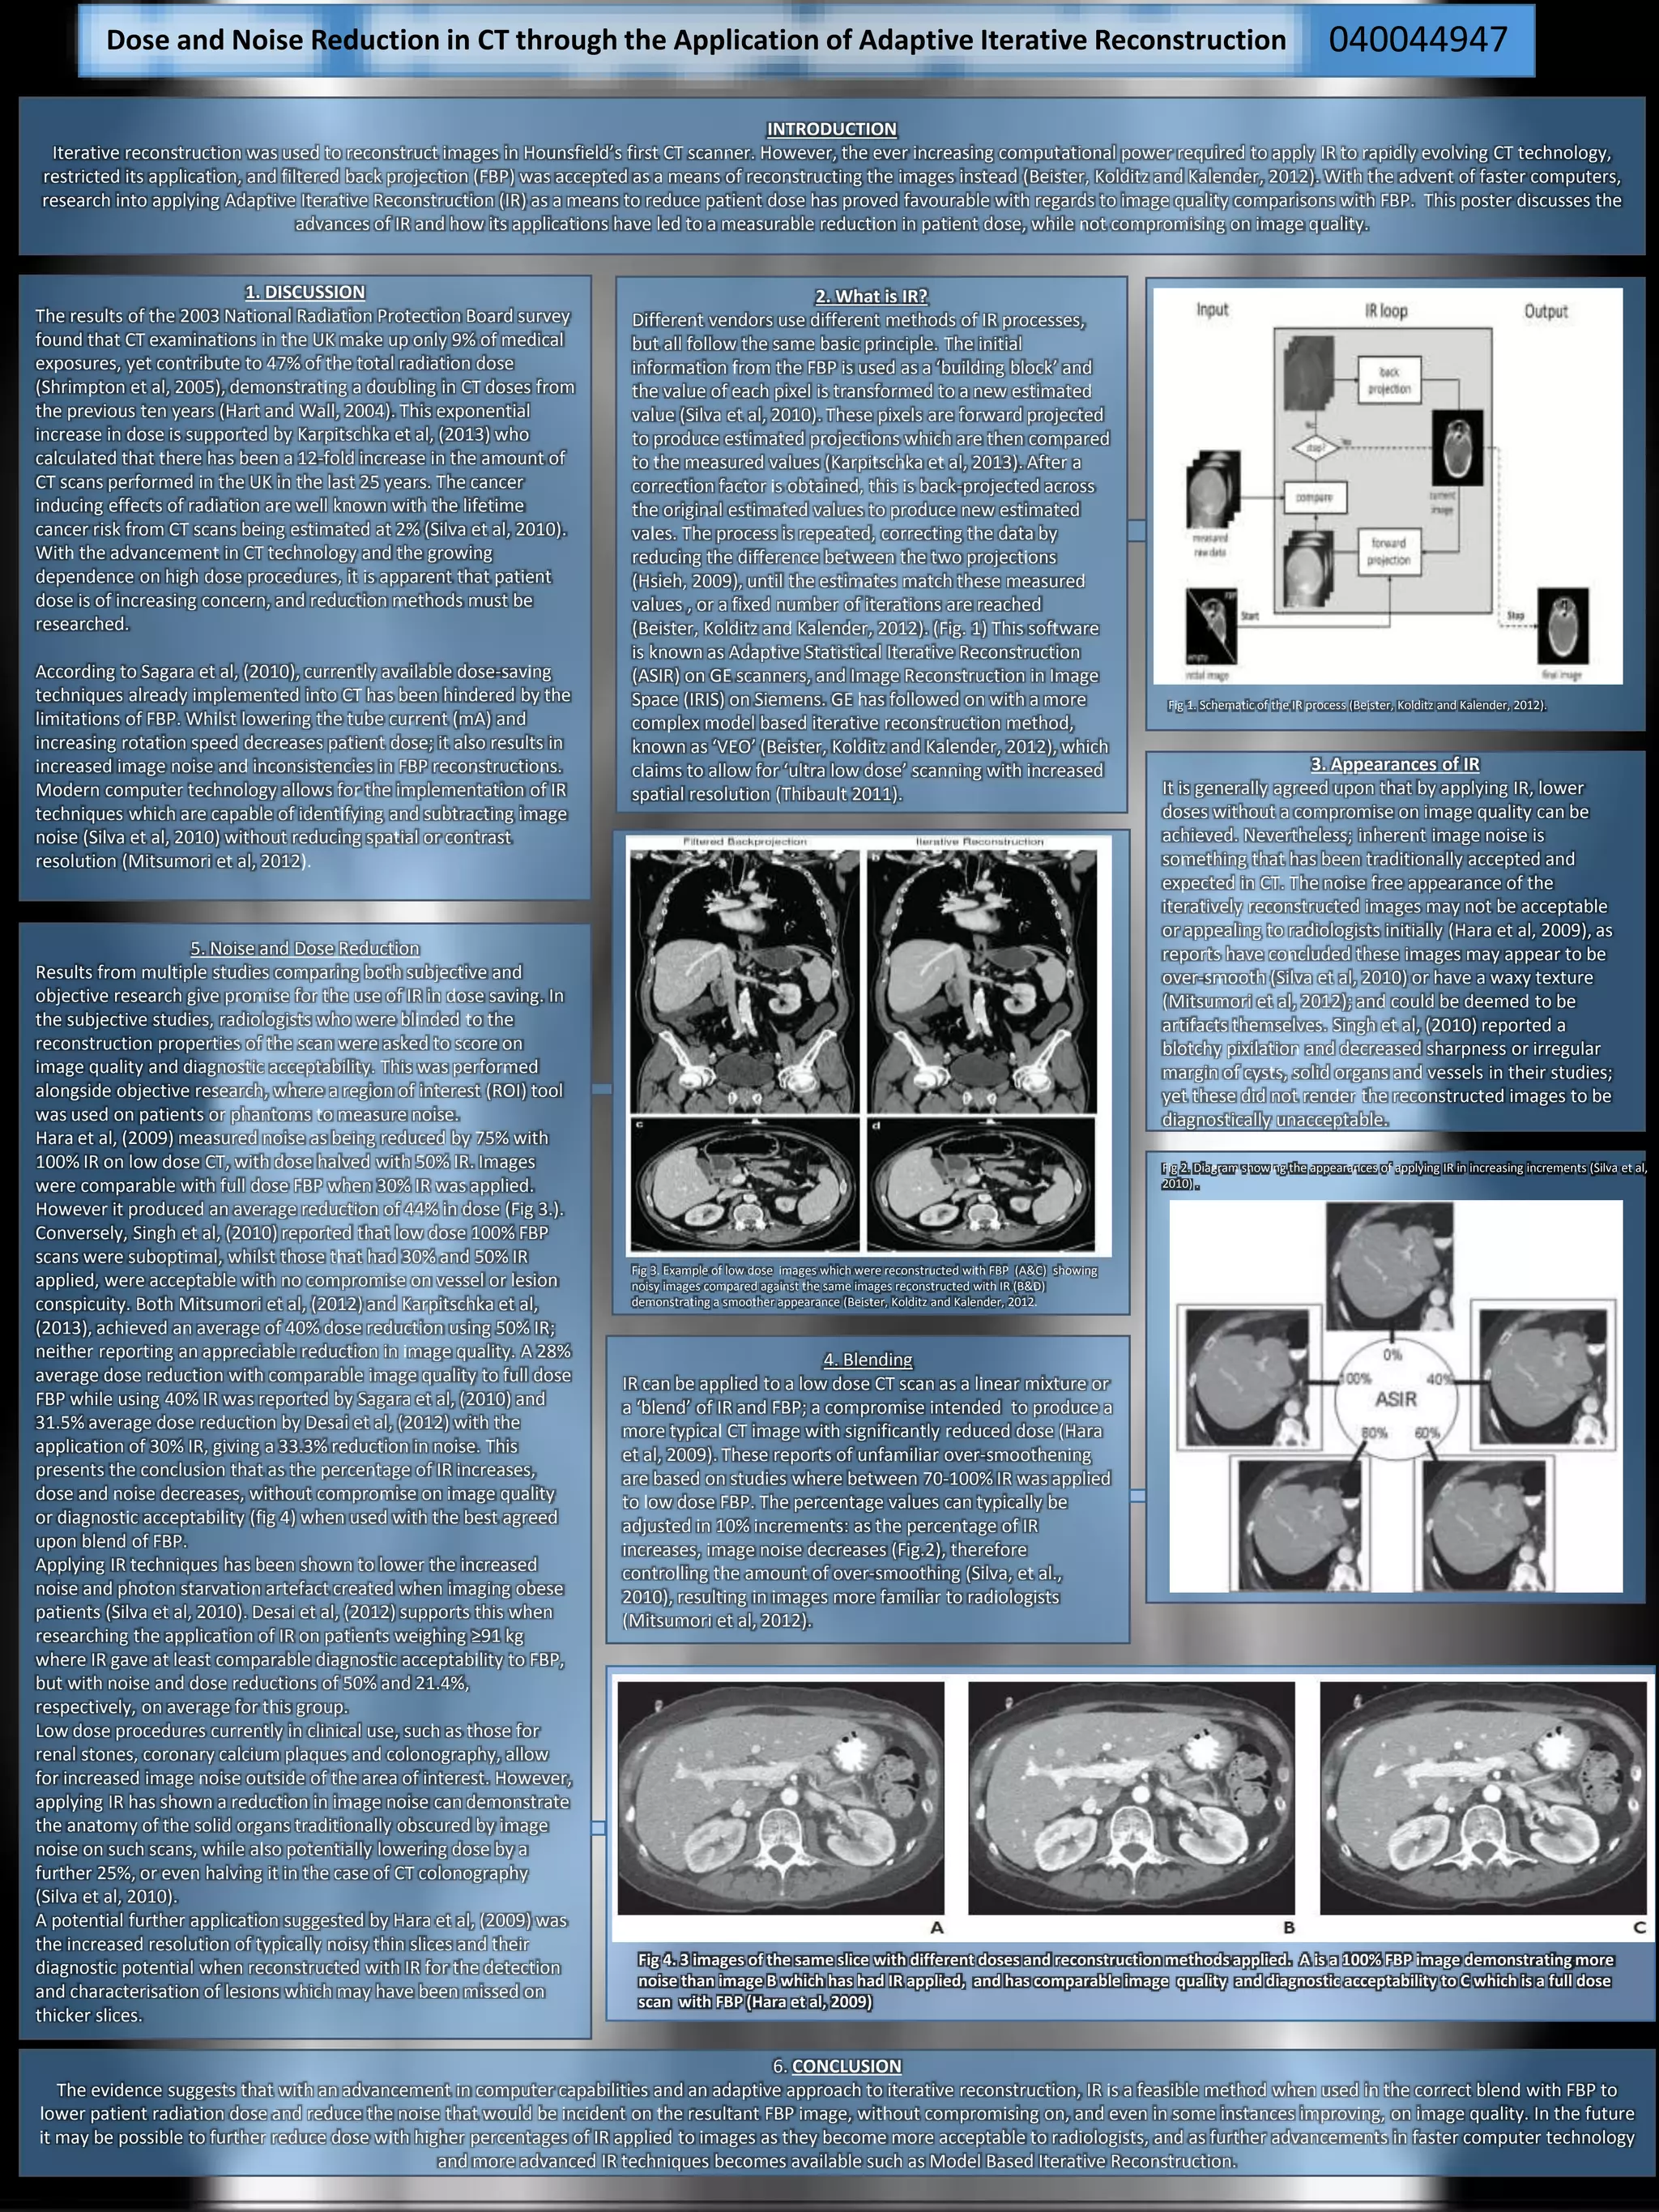

Fig 4. 3 images of the same slice with different doses and reconstruction methods applied. A is a 100% FBP image demonstrating more

noise than image B which has had IR applied, and has comparable image quality and diagnostic acceptability to C which is a full dose

scan with FBP (Hara et al, 2009)

5. Noise and Dose Reduction

Results from multiple studies comparing both subjective and

objective research give promise for the use of IR in dose saving. In

the subjective studies, radiologists who were blinded to the

reconstruction properties of the scan were asked to score on

image quality and diagnostic acceptability. This was performed

alongside objective research, where a region of interest (ROI) tool

was used on patients or phantoms to measure noise.

Hara et al, (2009) measured noise as being reduced by 75% with

100% IR on low dose CT, with dose halved with 50% IR. Images

were comparable with full dose FBP when 30% IR was applied.

However it produced an average reduction of 44% in dose (Fig 3.).

presents the conclusion that as the percentage of IR increases,

dose and noise decreases, without compromise on image quality

or diagnostic acceptability (fig 4) when used with the best agreed

upon blend of FBP.